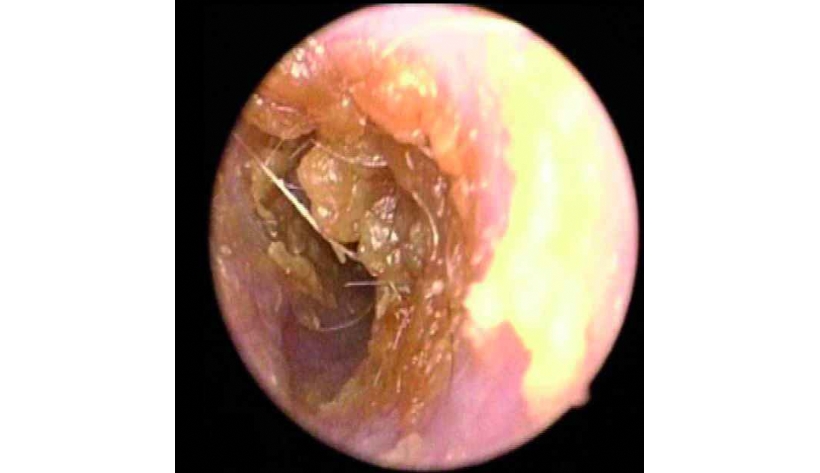

Mercredi 12 Mars 2025 Animaux de compagniePhoto n° 1 : Cérumen jaunâtre abondant obstruant partiellement le MAE visualisé en vidéo-otoscopie.